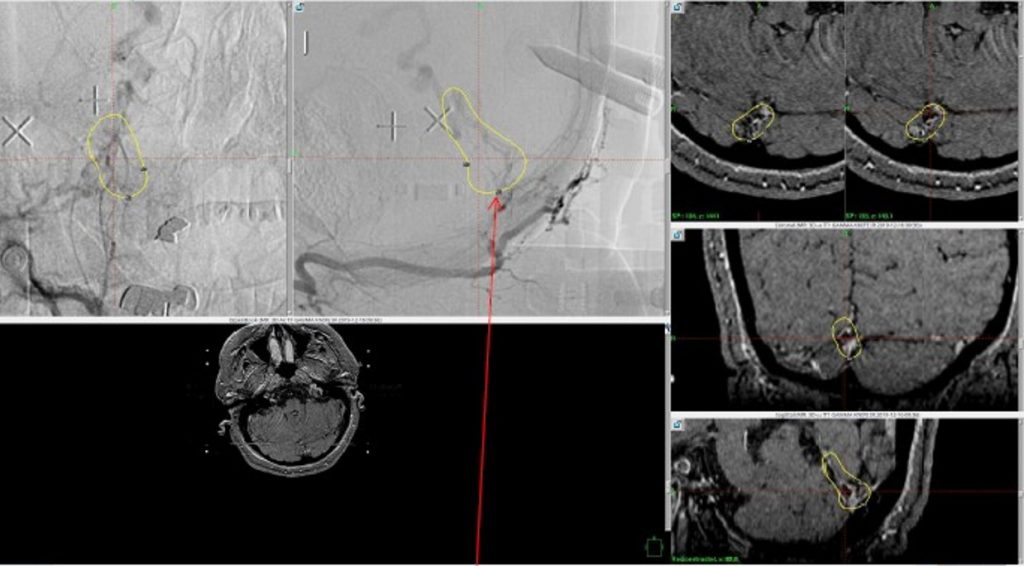

Figure 6. MRI and Catheter Angiograms precisely localize the residual A-V shunts vessels to perform Gamma-Knife Radiosurgery to deliver therapeutic doses to the targets.

Over the 12 to 18 months, she continued to remain event-free and maintain her active independent lifestyle. Delayed angiography over that period confirmed complete obliteration of the Left ECA and Vertebral Artery shunts with near complete obliteration of the Right ECA shunts (Figure 7).

Figure 7. 12 mos follow-up angiograms confirm complete obliteration of the left ECA and Vertebral Supply to the AVM, with a small late-filling component from the right Occipital artery that is markedly Reduced in size and flow (top row). Near complete resolution of the aneurysm and hematoma Is observed on 16 mos post Gamma Knife MRI (bottom row).